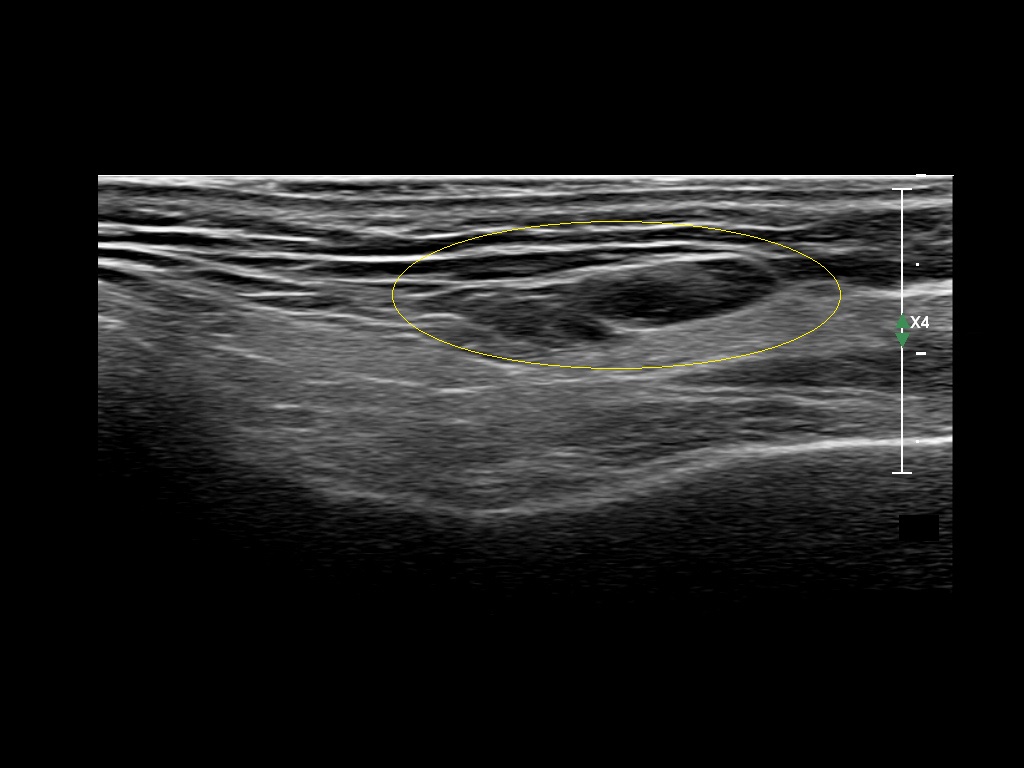

Filler injections in the parotid gland may go unnoticed, however, inflammatory reactions and abscesses may occur. Hypervascularity can be seen with color doppler. Filler deposits are supposed to be injected into the superficial fatty layer . The space to inject into this layer may be limited. Routinely we measure a width of 2-4 millimeters with sometimes subcutaneous layers being less than one millimeter thick.

Hover over an image to view the secondary image or click on the image title for more information.